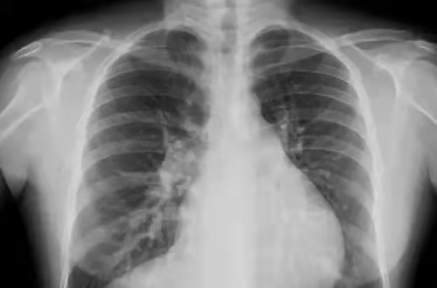

影像舉例

胸片能夠顯現(xiàn)我們的肺、心臟、縱膈、氣管,這么多器官都在一張片子上,所有器官的影像前后壓縮,變成了一張平片。所以,X線片是很多器官重疊在一起。

但是,如果肺部顯示有陰影,是肺結(jié)核?肺炎?還是腫瘤?X線是不能辨別的。

X線檢查

原理簡介:人體內(nèi)部組織的密度不同,所以射線穿過身體時有些地方能穿透,有些地方不能穿透。比如肺被穿透后,在X線片上就是黒的,因為它沒有阻擋,膠片能夠全部曝光,所以呈現(xiàn)出來是黑的。而骨骼不容易穿透,顯示出來就是白的。

應(yīng)用:主要看密度,擅長骨折、肺臟病變等

優(yōu)點:作用廣、快捷、檢查費用低;

缺點:受制于深淺組織的影像相互重疊和隱藏,有時需要多次多角度拍片才能看清楚;